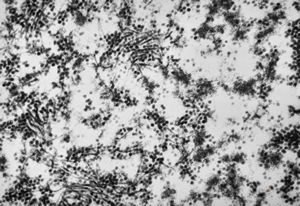

M,10y. | herpetic encephalitis